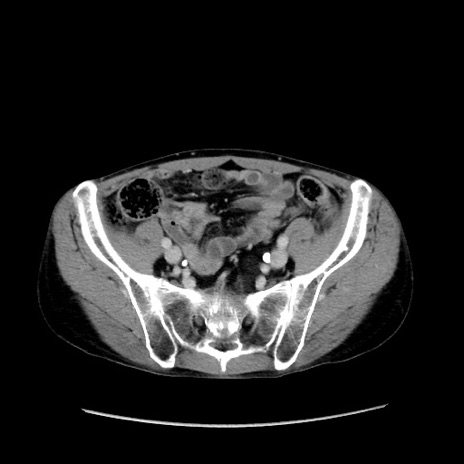

症例37(横断像)

【症例】40歳代 男性

【主訴】腹痛

【現病歴】4時間ほど前に電車に乗車中に臍部上より腹痛出現。徐々に増悪し起立困難となり、救急外来受診。生ものは数日食べていない。今朝お雑煮を食べた。

【身体所見】BT 36.8℃、BP 117/84mmHg、HR 91/min、SpO2 97%、苦悶様、腹部:臍上部広範囲圧痛あり、反跳痛±

【データ】WBC 8100、CRP 0.03